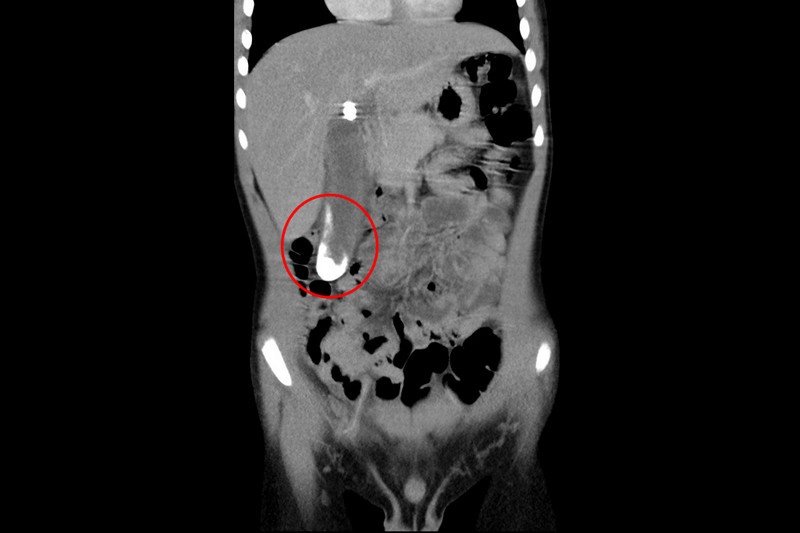

圖說:紅色圈起處為陳小弟體內發炎腫脹的膽囊,白色部分為膽結石

二零二二年八月中旬,六歲的陳小弟因腹痛不止而就醫,經超音波和電腦斷層檢查,發現膽囊裡竟有大片膽結石堵住與膽管的銜接處,造成發炎、引起疼痛,在花蓮慈濟醫院小兒部陳明群與張雲傑醫師的會診後,判斷陳小弟是罕見的「小兒膽結石」。

透過超音波與電腦斷層確認,陳小弟的膽囊中有一些細小的結石,不僅是罕見的小兒膽結石,更是極少在這個年齡段發生的案例。考慮到孩子並沒有家族病史,也無常見形成小兒膽結石的危險因子,張雲傑主任與家屬討論過後,先使用藥物控制,以內科療法治療,讓結石不要持續增大;直到後續陳小弟再次就醫,發現結石情況並無好轉,甚至已逐漸連成一大片,卡在膽囊管進總膽管處,造成慢性發炎。由於內科治療無法使病況緩解,小兒科張雲傑醫師照會楊筱惠醫師與兒童外科團隊,討論為陳小弟開刀摘除膽囊的可能性。